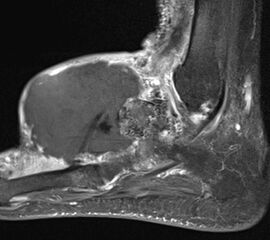

MR-tomographische Darstellung eines unspezifischen weichteiligen Raumforderug im Bereich des dorso-lateralen Rückfußes. Die offene Probebiopsie ergab schließlich die Diagnose eines hochmalignen Synovialsarkoms.

Abbildung 34